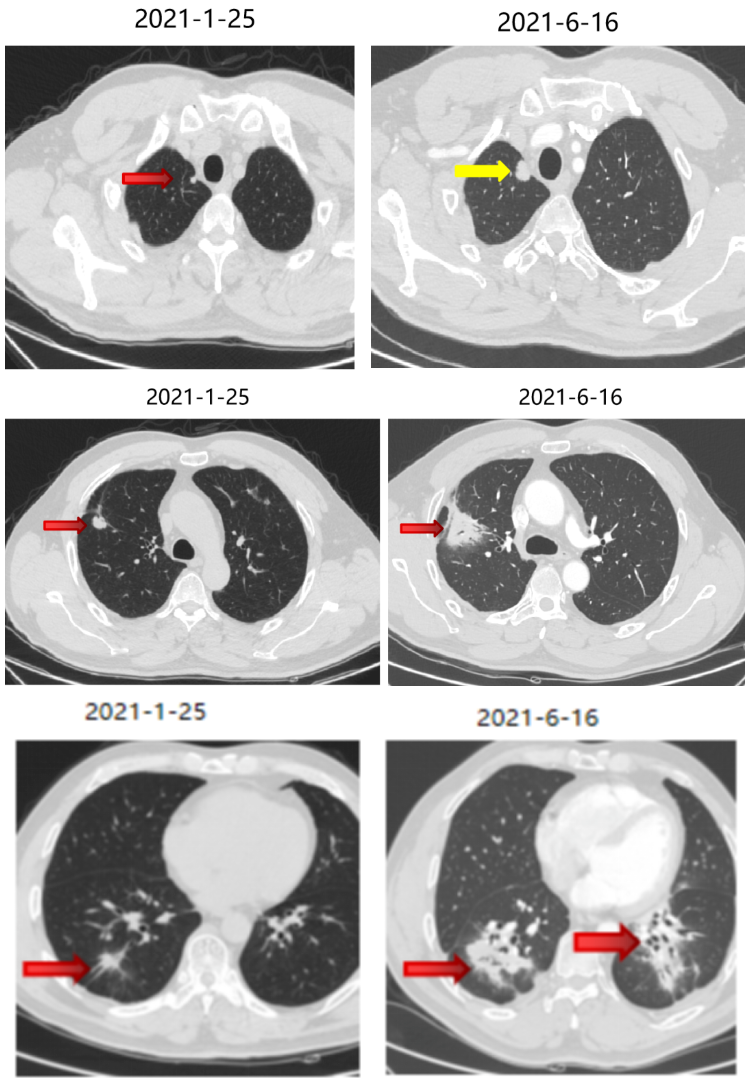

三线治疗

2021-1 起口服呋喹替尼3mg +曲妥珠单抗。

期间2021-3-15胸部CT:双肺转移瘤部分较前略增大,疗效SD。

三线治疗疗效评价:部分增大,PD。

四线治疗

2021-6-17 起口服曲氟尿苷替匹嘧啶片(TAS-102)40mg bid。

四线治疗疗效:部分略减小,SD。